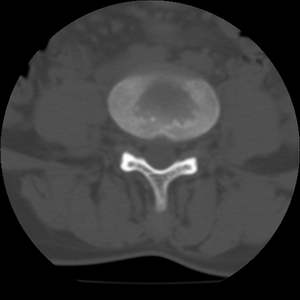

标题: CT21469:腰椎局限性呈高密度,什么原因? [打印本页]

标题: CT21469:腰椎局限性呈高密度,什么原因?

34y,做腰椎间盘扫描发现的,战友们讨论一下原因!

骨质增生硬化

腰椎前缘密度较均匀增高,边缘清晰;考虑腰椎致密性骨炎可能。

考虑骨岛。患者增生硬化不明显,男34岁,腰椎非致密性骨炎好发部位、性别。

支持致密性骨炎,腰椎前缘也是致密性骨炎好发位置.

致密性骨炎好发部位于青壮年女性的双骶髂关节,腰椎上的我还没见过。

考虑腰椎致密性骨炎,其实腰椎前上角是也是致密性同炎的好发部位,只是没能引起同志们的注意。